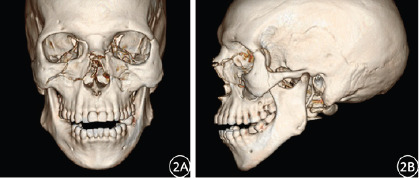

Results: In this study, 52 cases of maxillofacial fractures with a total of 83 fractures were diagnosed by 2D CT reconstruction technology, with a fracture detection rate of 77.61% (52/67). Using 3D CT reconstruction technology, 54 cases of maxillofacial fractures with a total of 91 fractures were diagnosed, and the fracture detection rate was 80.60% (54/67). Statistical analysis showed no significant difference in the detection rate of maxillofacial fractures between 2D CT and 3D CT reconstruction (χ2 = 35.945, P = 0.687). In the diagnosis of zygomatic fractures, nasal fractures, and upper and lower jaw fractures, 3D CT reconstruction images have obvious advantages over 2D CT in displaying fracture displacement and fracture line course. However, for the display of comminuted fractures combined with sphenoid and ethmoid fractures, the cross-sectional images of 2D CT show higher superiority.

Conclusion: 2D CT reconstruction is a basic diagnostic tool for maxillofacial fractures. 3D reconstruction, with high detection and multi-angle visualization, offers valuable imaging for clinical decision-making, aiding in surgery planning. A combined approach, leveraging the strengths of both modalities, is pivotal for comprehensive assessment and management of maxillofacial trauma.